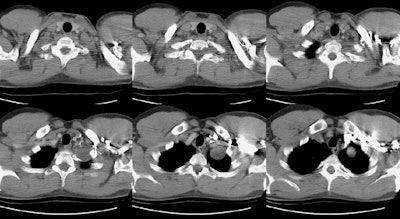

Schwannoma:

The CT scan revealed a homogeneous low density mass within the left lung apex- on careful evaluation, the mass could be seen extending outside the thoracic cavity and into the T1 neural foramena (middle image on top row) (Click here to view bone windows).